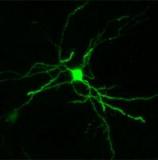

Новое исследование показало, что найден общий механизм возникновения различных заболеваний, затрагивающих развитие и работу мозга. Синдром Ретта, синдром Корнели де Ланге, синдром альфа-талассемии и олигофрении, Х-сцепленный синдром – вызваны различными расстройствами в хроматине, белках и ДНК, из которых состоят хромосомы. Они же отвечают за чтение генетической информации. Совершенно разные заболевания, связанные с дисфункцией хроматина, часто приводит к одинаковым клиническим симптомам. Поврежденные белки нуждаются друг в друге для работы в определенных импринтных генах. Эти гены несут различную информацию в зависимости от того, кто был ее передатчиком – мать или отец. Например, белок, измененный при Х-сцепленном синдроме, регулируют работу импринтных генов и генов, влияющих на развитие мозга. Данное исследование впервые пояснило связь между связанными генетическими синдромами. Необходимо провести дальнейшие исследования, чтобы лучше понять роль белка хроматина. Источник: Medicalnewstoday

Медики предполагают, что суицидальные наклонности могут быть обусловлены генетическими нарушениями, влияющими на рост нервных клеток. Ученые из Германии и США, которые занимались этим вопросом, считают, что склонность к совершению попыток самоубийства определяется наследственными факторами. Они выявили пять мононуклеотидных мутаций, которые часто встречаются у людей, склонных к самоубийству. Три мутации из этих пяти повышают вероятность попытки суицида в 4,5 раза. Суицидальные наклонности могут передаваться по наследствуУченые исследовали генотип 394 пациентов, страдающих депрессией, 113 из которых пытались покончить с собой. Затем они сравнили их ДНК с наследственной информацией 366 здоровых людей. При помощи анализа этих данных медики выявили пять генетических изменений, которые особенно часто наблюдались у больных с суицидальными наклонностями. Эти выводы подтверждают результаты другого исследования, в котором приняли участие 1600 немцев и афроамериканцев. 270 из них совершали попытки суицида. Кроме того, выводы ученых перекликаются с рядом ранее опубликованных научных работ, в которых говорится о том, что в некоторых семьях суицидальные наклонности явно передаются по наследству. Изменения генотипа, называемые также мононуклеотидным полиморфизмом, затрагивают два гена, которые влияют на формирование и рост нервных клеток. Носители трех наиболее опасных мутаций совершают самоубийство в 4,5 раза чаще других. Исследованием руководили доктор Мартин Коли (Martin Kohli) из Института психиатрии имени Макса Планка в Мюнхене, Германия, и доктор Джон Хьюссман (John P. Hussman) из Института генетики человека в Майами, США. В отчете о проделанной ими работе, который был опубликован в Archives of General Psychiatry, ученые пишут: «Исследования семей и близнецов показывают, что склонность к совершению самоубийства или попыток самоубийства является наследственным фактором. Комплекс биологических признаков, связанных с завершенной или незавершенной попыткой самоубийства, часто встречается у членов отдельных семей. При этом наличие наследственных факторов, связанных с суициальными наклонностями, по-видимому, никак не связано с наличием тех или иных психических заболеваний».